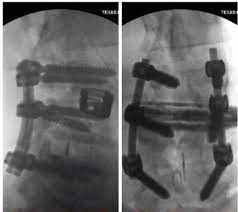

پس از آخرین مسابقه کلمن در سال ۲۰۰۷، او موافقت کرد که مشکلات کمر و فتق دیسک خود را برطرف کند. سپس یک سری از جراحیها با موفقیت اندک و جزئی روی کمر او انجام شد. در مجموع، کلمن ۱۳ زیر تیغ جراحی رفت. در حال حاضر ستون فقرات او به طور کامل به هم جوش خورده است، غیر از یک دیسک که بعدها دچار دررفتگی شد.

من ۱۴ پیچ، دو قفس و دو میله در ستون فقراتم دارم. در کنار تمامی اتفاقات ناگوار، این شخصیت کلمن است که علاقهمندان به تناسب اندام را جذب خود میکند. او با وجود درد لبخند میزند و امید خود برای بهبودی را از دست نداده است. در سالهای اخیر، این اسطوره به دنبال اشکال مختلف درمانی بوده تا بتواند دوباره روی پای خود بایستد.